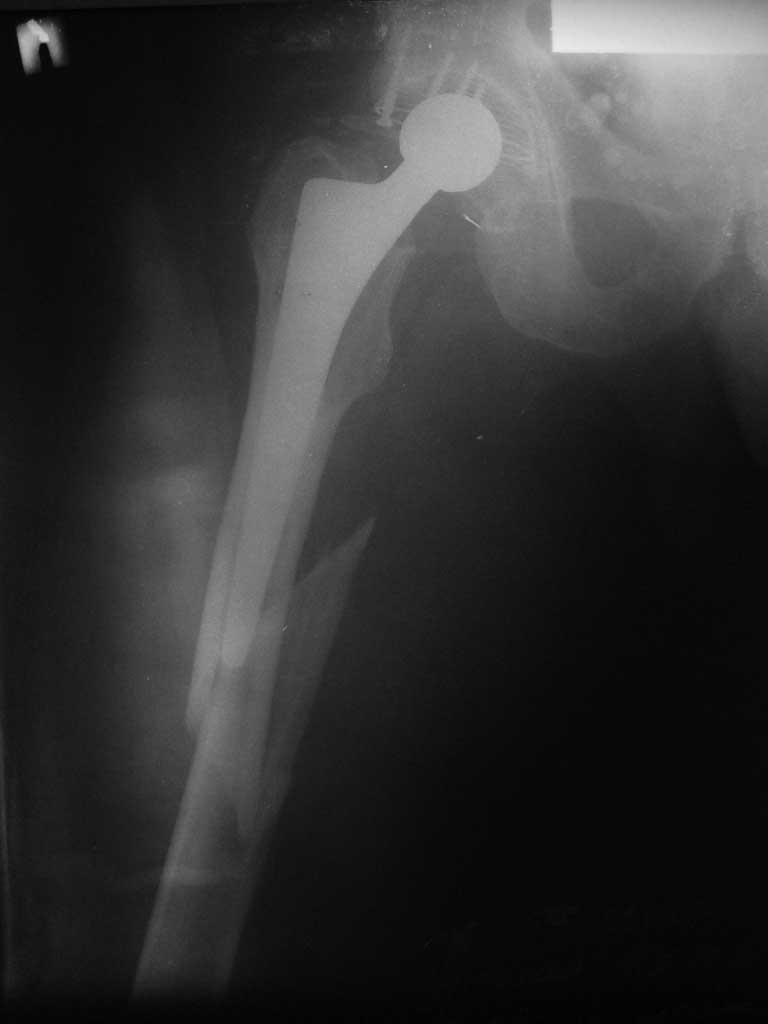

Уважаемые коллеги, продолжая дискуссию, начатую на "Вреденовских чтениях", хочу сказать, что принципиально сущестует два возможных варианта лечения.

1.Остеосинтез на ножке. Мне кажется, что применительно к этому случаю малоперспективный вариант. Синтез хорош, когда можно его выполнить в малоинвазивном исполнении и достигнуть стабильности. Действительно, если ножка б/цементной фиксации после этого не будет иметь фиксации, то ревизия не будет иметь проблем. В представленном случае стабильность синтеза сомнительная, а проведение доп.иммобилизации приведет к контрактуре суставов.

2. Применение ножки дистальной фиксации, мы отдаем предпочтение ножке Вагнера с фиксацией проксимального отдела на ножке. Более травматичное вмешательство, но при стабильной фиксации ножки реабилитация идет в обычном режиме.

Хочется показать два подобных случая, П-ка З. 72 лет и п-т Г. 80 лет. Сразу принимаю замечание, что это были ножки цементной фиксации, просто под руками не было бесцементника.

Пациента удалось осмотреть недавно. Достигнутый результат сохраняется. Перелом бедра сросся. Конечность опорная и безболезненная, ходит без трости. Ножка, похоже, реинтегрировалась, как и надеялись. Снимки и фото в приложении. Комментарии приветствуются.

Надо ли что-то делать дальше, как полагаете? Убрать винты? Убрать "удлинитель ножки"? Или оставить все, как есть? Спасибо заранее.